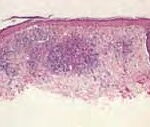

Superficial Basal Cell Carcinoma

Superficial BCC is characterized microscopically by buds of malignant cells extending into the dermis from the basal layer of the epidermis. The peripheral cell layer shows palisading. There may be epidermal atrophy, and dermal invasion is usually minimal. This histologic sub-type is encountered most often on the trunk and extremities but may also appear on the head and neck. There may be a chronic inflammatory infiltrate in the upper dermis.